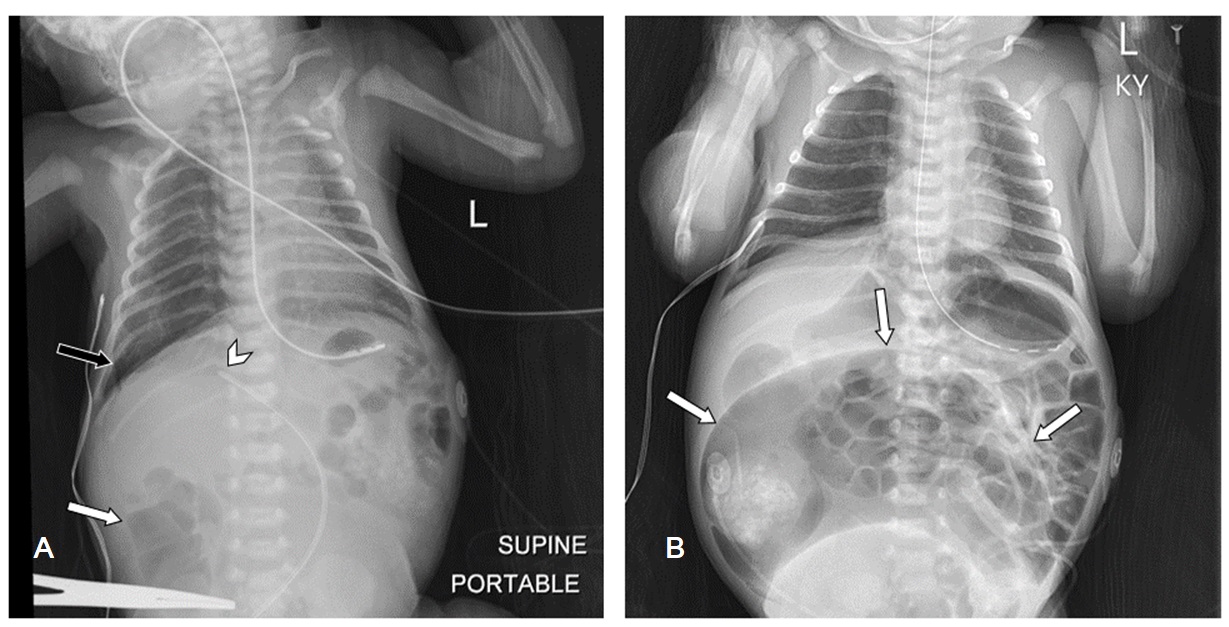

Chest and abdomen radiographs approximately 14 hours apart demonstrating rapid progression of bowel dilation. A) Day of life 0 radiograph shows a nonobstructive bowel gas pattern with mild distention of the right colon (white arrow). Note the malpositioned umbilical venous catheter-directed towards the right portal vein (arrowhead) and small right pneumothorax (black arrow). B) Day of life 1 radiograph shows massive gaseous dilation of the congenital sigmoid pouch colon (arrows).

Figure 3